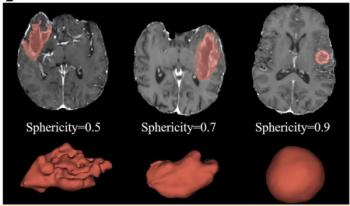

Low tumor sphericity on preoperative MRI is associated with a significantly higher mortality rate in patients with IDH-wildtype glioblastoma, according to a new study.